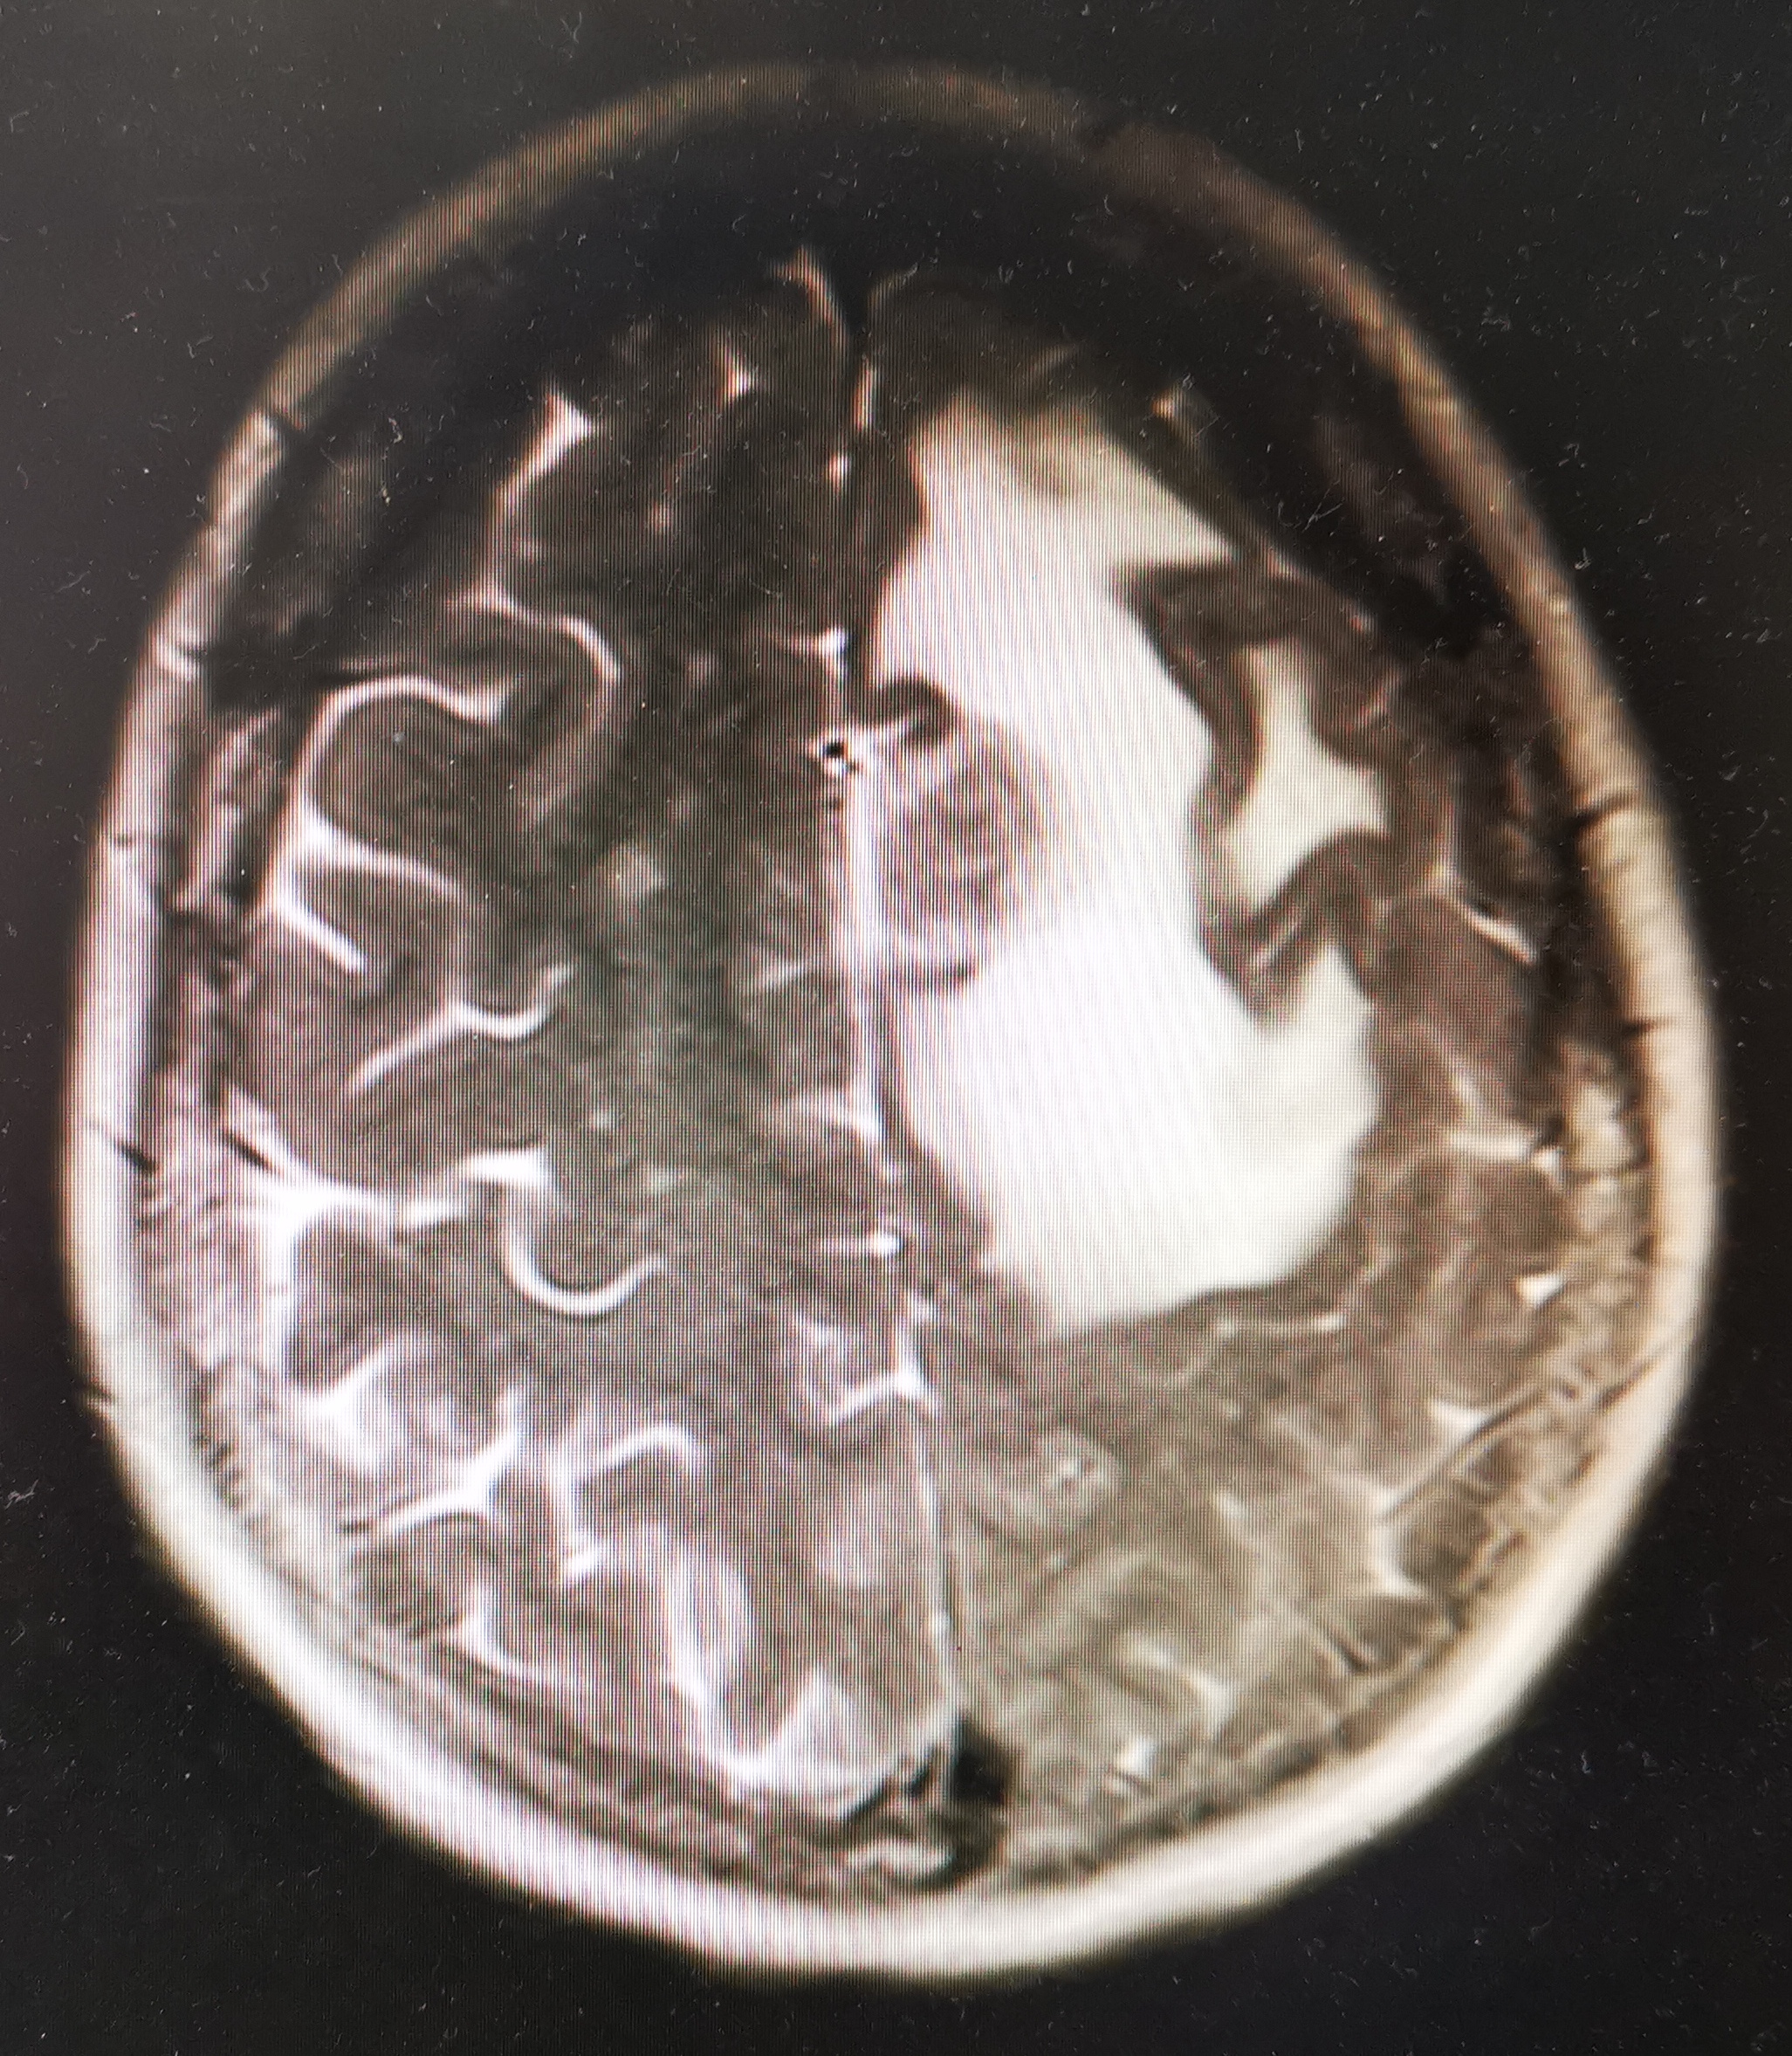

一刻钟后她回来了,这时我已经打开了她的影像图片,很遗憾,电脑显示出现大面积异常信号区,很明确的转移了!看到她绝望的神情,以及伤心的哭泣声,我痛苦极了。

肺癌图片 脑转移图片

脑转移MRI图片